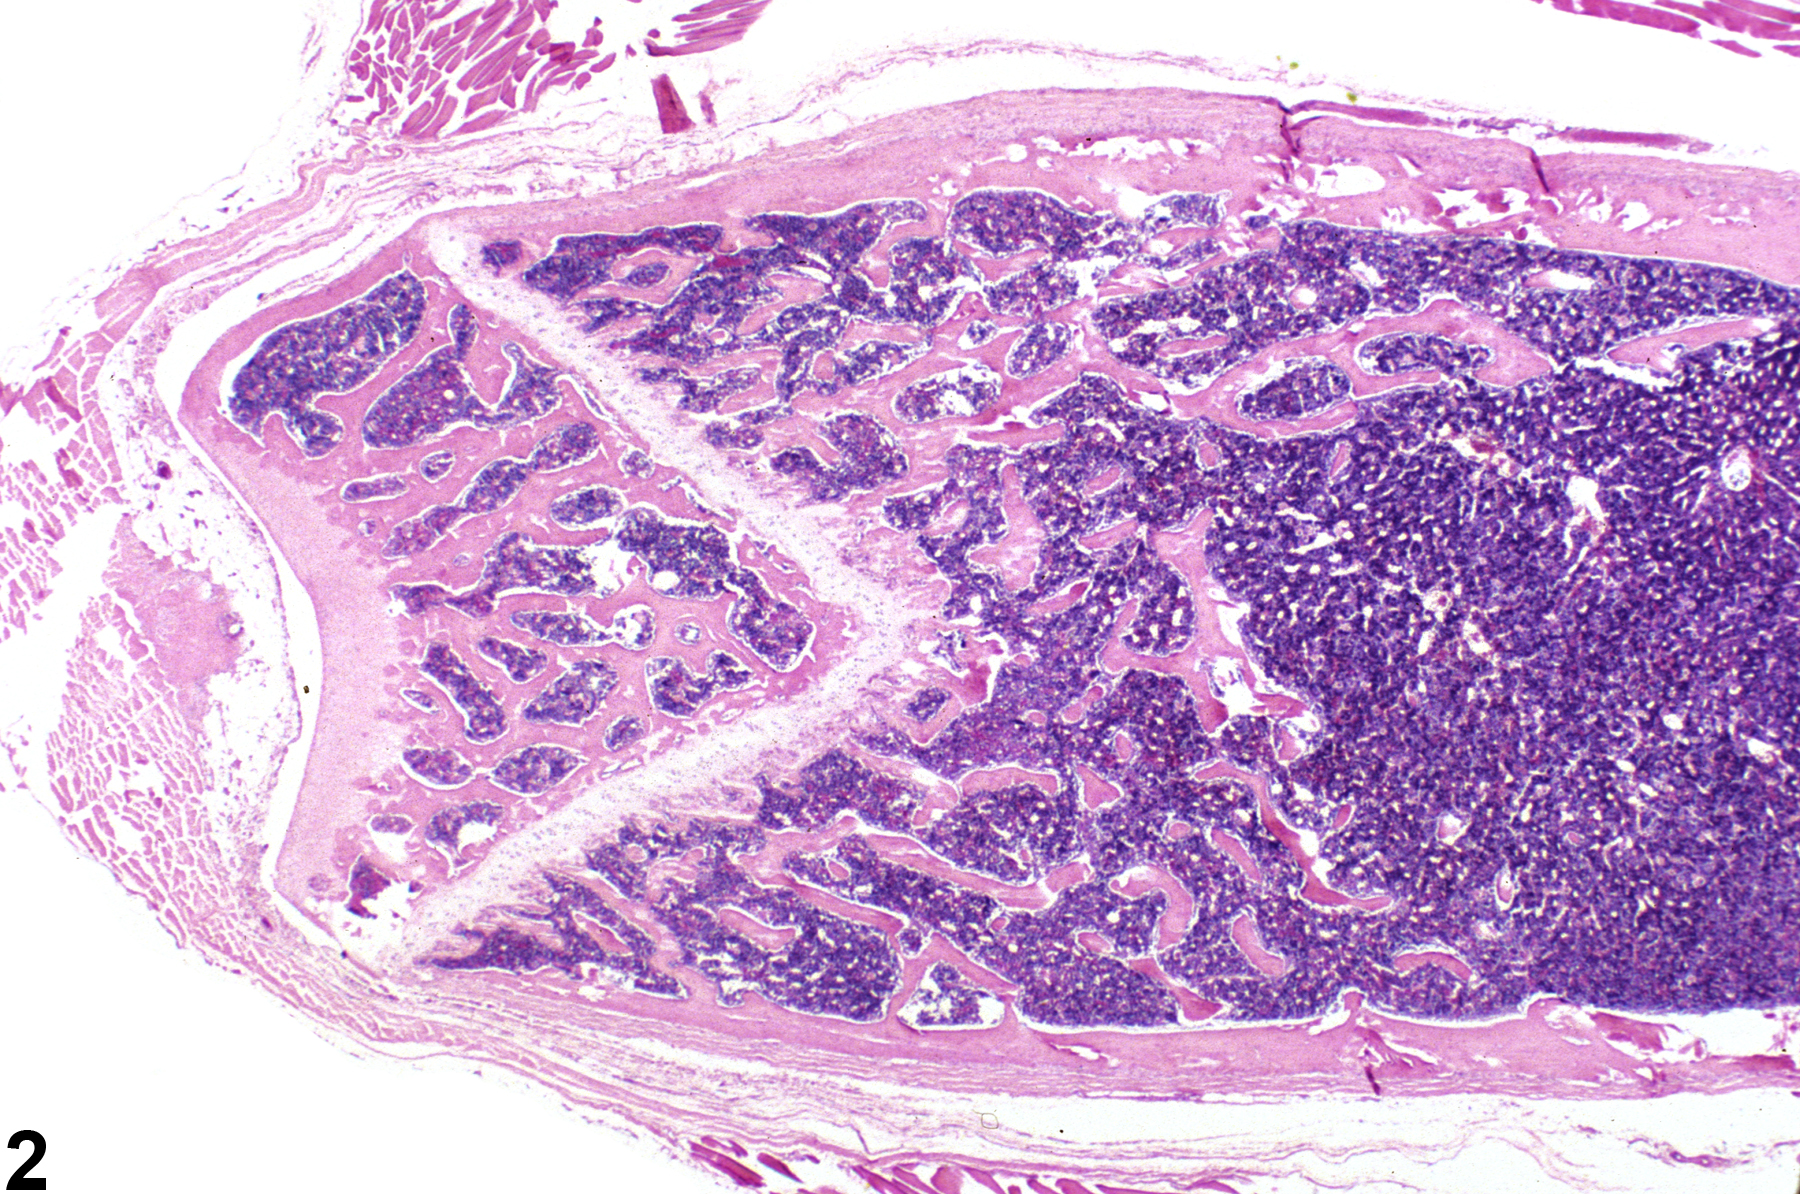

Hypercellularity of the bone marrow is recorded in treated animals when there is an increase in hematopoietic cells relative to adipocytes compared with concurrent controls (Figure 2, Figure 4, and Figure 5). Hypercellularity may occur as a nonspecific or direct (e.g., with cytokine administration) response to compound administration but more commonly is due to a regenerative response as a consequence of decreases in peripheral blood cells, recovery from a xenobiotic-induced bone marrow injury, or inflammation. For example, hypercellularity may be secondary to sepsis or a result of blood loss, hemolytic anemia or platelet consumption/destruction. Stimulation to produce more of one cell line can cause increased production of other cell lines, causing an overall increase in bone marrow cellularity. With marked hypercellularity, hematopoietic cells may fill the entire marrow space, even extending through the nutrient foramina.

Bone marrow in a control female F344 rat from a subchronic study.